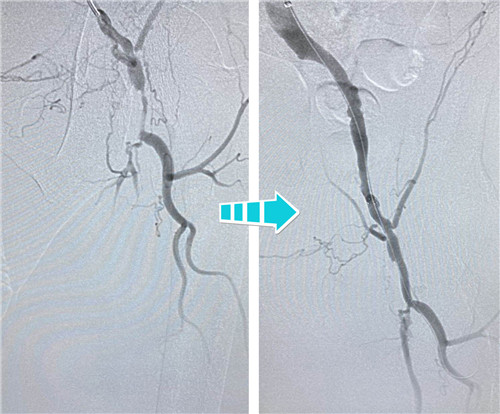

身經(jīng)百戰(zhàn)的放射科介入團(tuán)隊(duì),在南京鼓樓醫(yī)院血管外科王煒教授的指導(dǎo)下,決定為吳老先生行兩側(cè)髂血管成形術(shù)。手術(shù)當(dāng)天,選擇經(jīng)左側(cè)肱動(dòng)脈入路,置入90CM長(zhǎng)鞘,在導(dǎo)絲指引下,小心翼翼地通過左側(cè)股總動(dòng)脈狹窄段,給予球囊擴(kuò)張,精確定位并植入支架,左側(cè)髂血管就此打通??紤]后期患者情況改善,可能還需要處理股淺動(dòng)脈,專家們還預(yù)保留了股淺和股深開口。

右側(cè)完全閉塞的髂血管順行開通無果,但這也難不倒我們經(jīng)驗(yàn)豐富的鼓醫(yī)和石醫(yī)介入專家們,當(dāng)即決定由“順穿”改行“逆穿”。逆穿導(dǎo)絲難度大,技術(shù)要求高,十分考驗(yàn)術(shù)者的操作手法和預(yù)判,專家團(tuán)隊(duì)經(jīng)過內(nèi)膜下破膜逆行,一次性準(zhǔn)確對(duì)吻成功,同樣擴(kuò)張球囊、植入支架,血流瞬間恢復(fù)暢通。

術(shù)后,吳老先生的癥狀明顯改善,腿不疼了,走路也利索了,晚上終于可以睡個(gè)安穩(wěn)覺了。